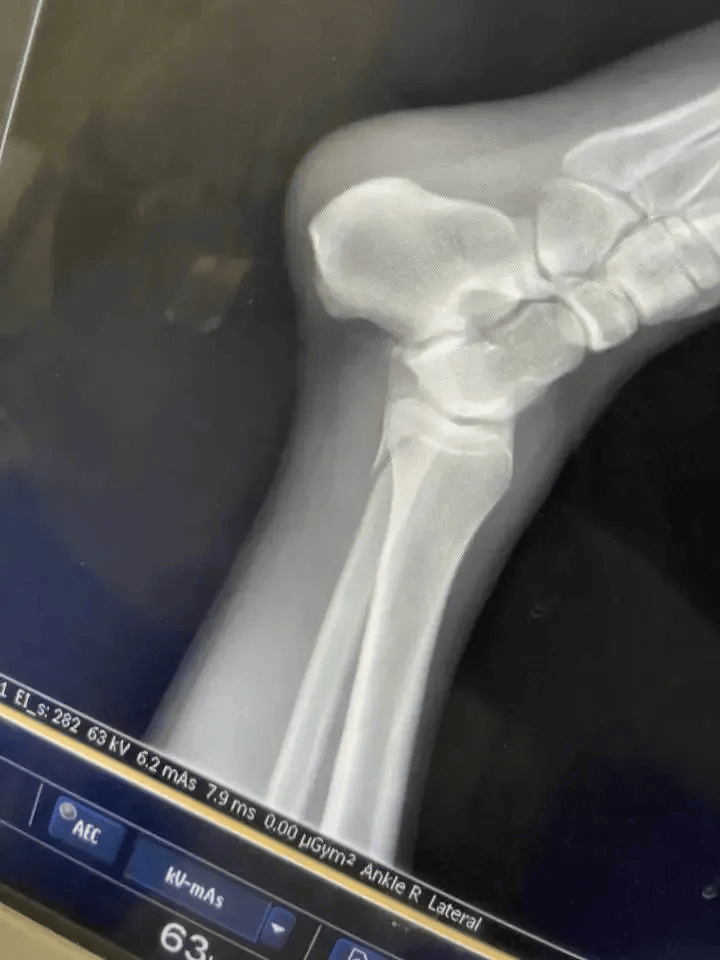

据橙柿互动,记者注意到,有受伤的女孩还在视频平台直播,讲述自己受伤的过程。女孩称,自己冲关时摔下来,腿都骨折了。

“我感觉水下有个不平的东西,当时一瞬间还没感觉脚崴了,硬撑着走上岸就走不动了,最后用一只脚蹦到救护车上。”

小董说,自己刚在救护车上躺下,又来了一个骨折的,是个小姐姐,看上去比自己更严重。“我就把躺的位置让给她,她的腿骨折了,我是踝骨受伤。现场的工作人员让我们到二级以上的公立医院治疗,然后报销。”“他说让我们联系保险公司处理。问他的身份,他说是综艺节目的人。问他职务,他说是负责后勤的。他一边处理我们的事情,一边电话请示。”

和小董一起去医院的姑娘叫小黄。小黄说,自己落水受伤后,腿已经肿起来,动不了。“从场地送到医院救护车的钱,都是我和小董一人一半自己付费的,连治疗费用都是我们自己垫付的。”